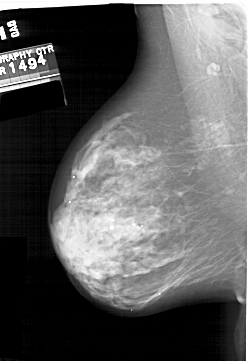

A_2000_1.LEFT_CC

LEFT_CC LINES 5971 PIXELS_PER_LINE 3916 BITS_PER_PIXEL 12 RESOLUTION 43.5 NON_OVERLAY